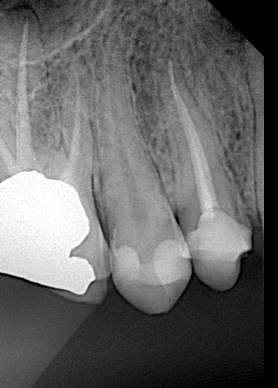

X ray after biobase